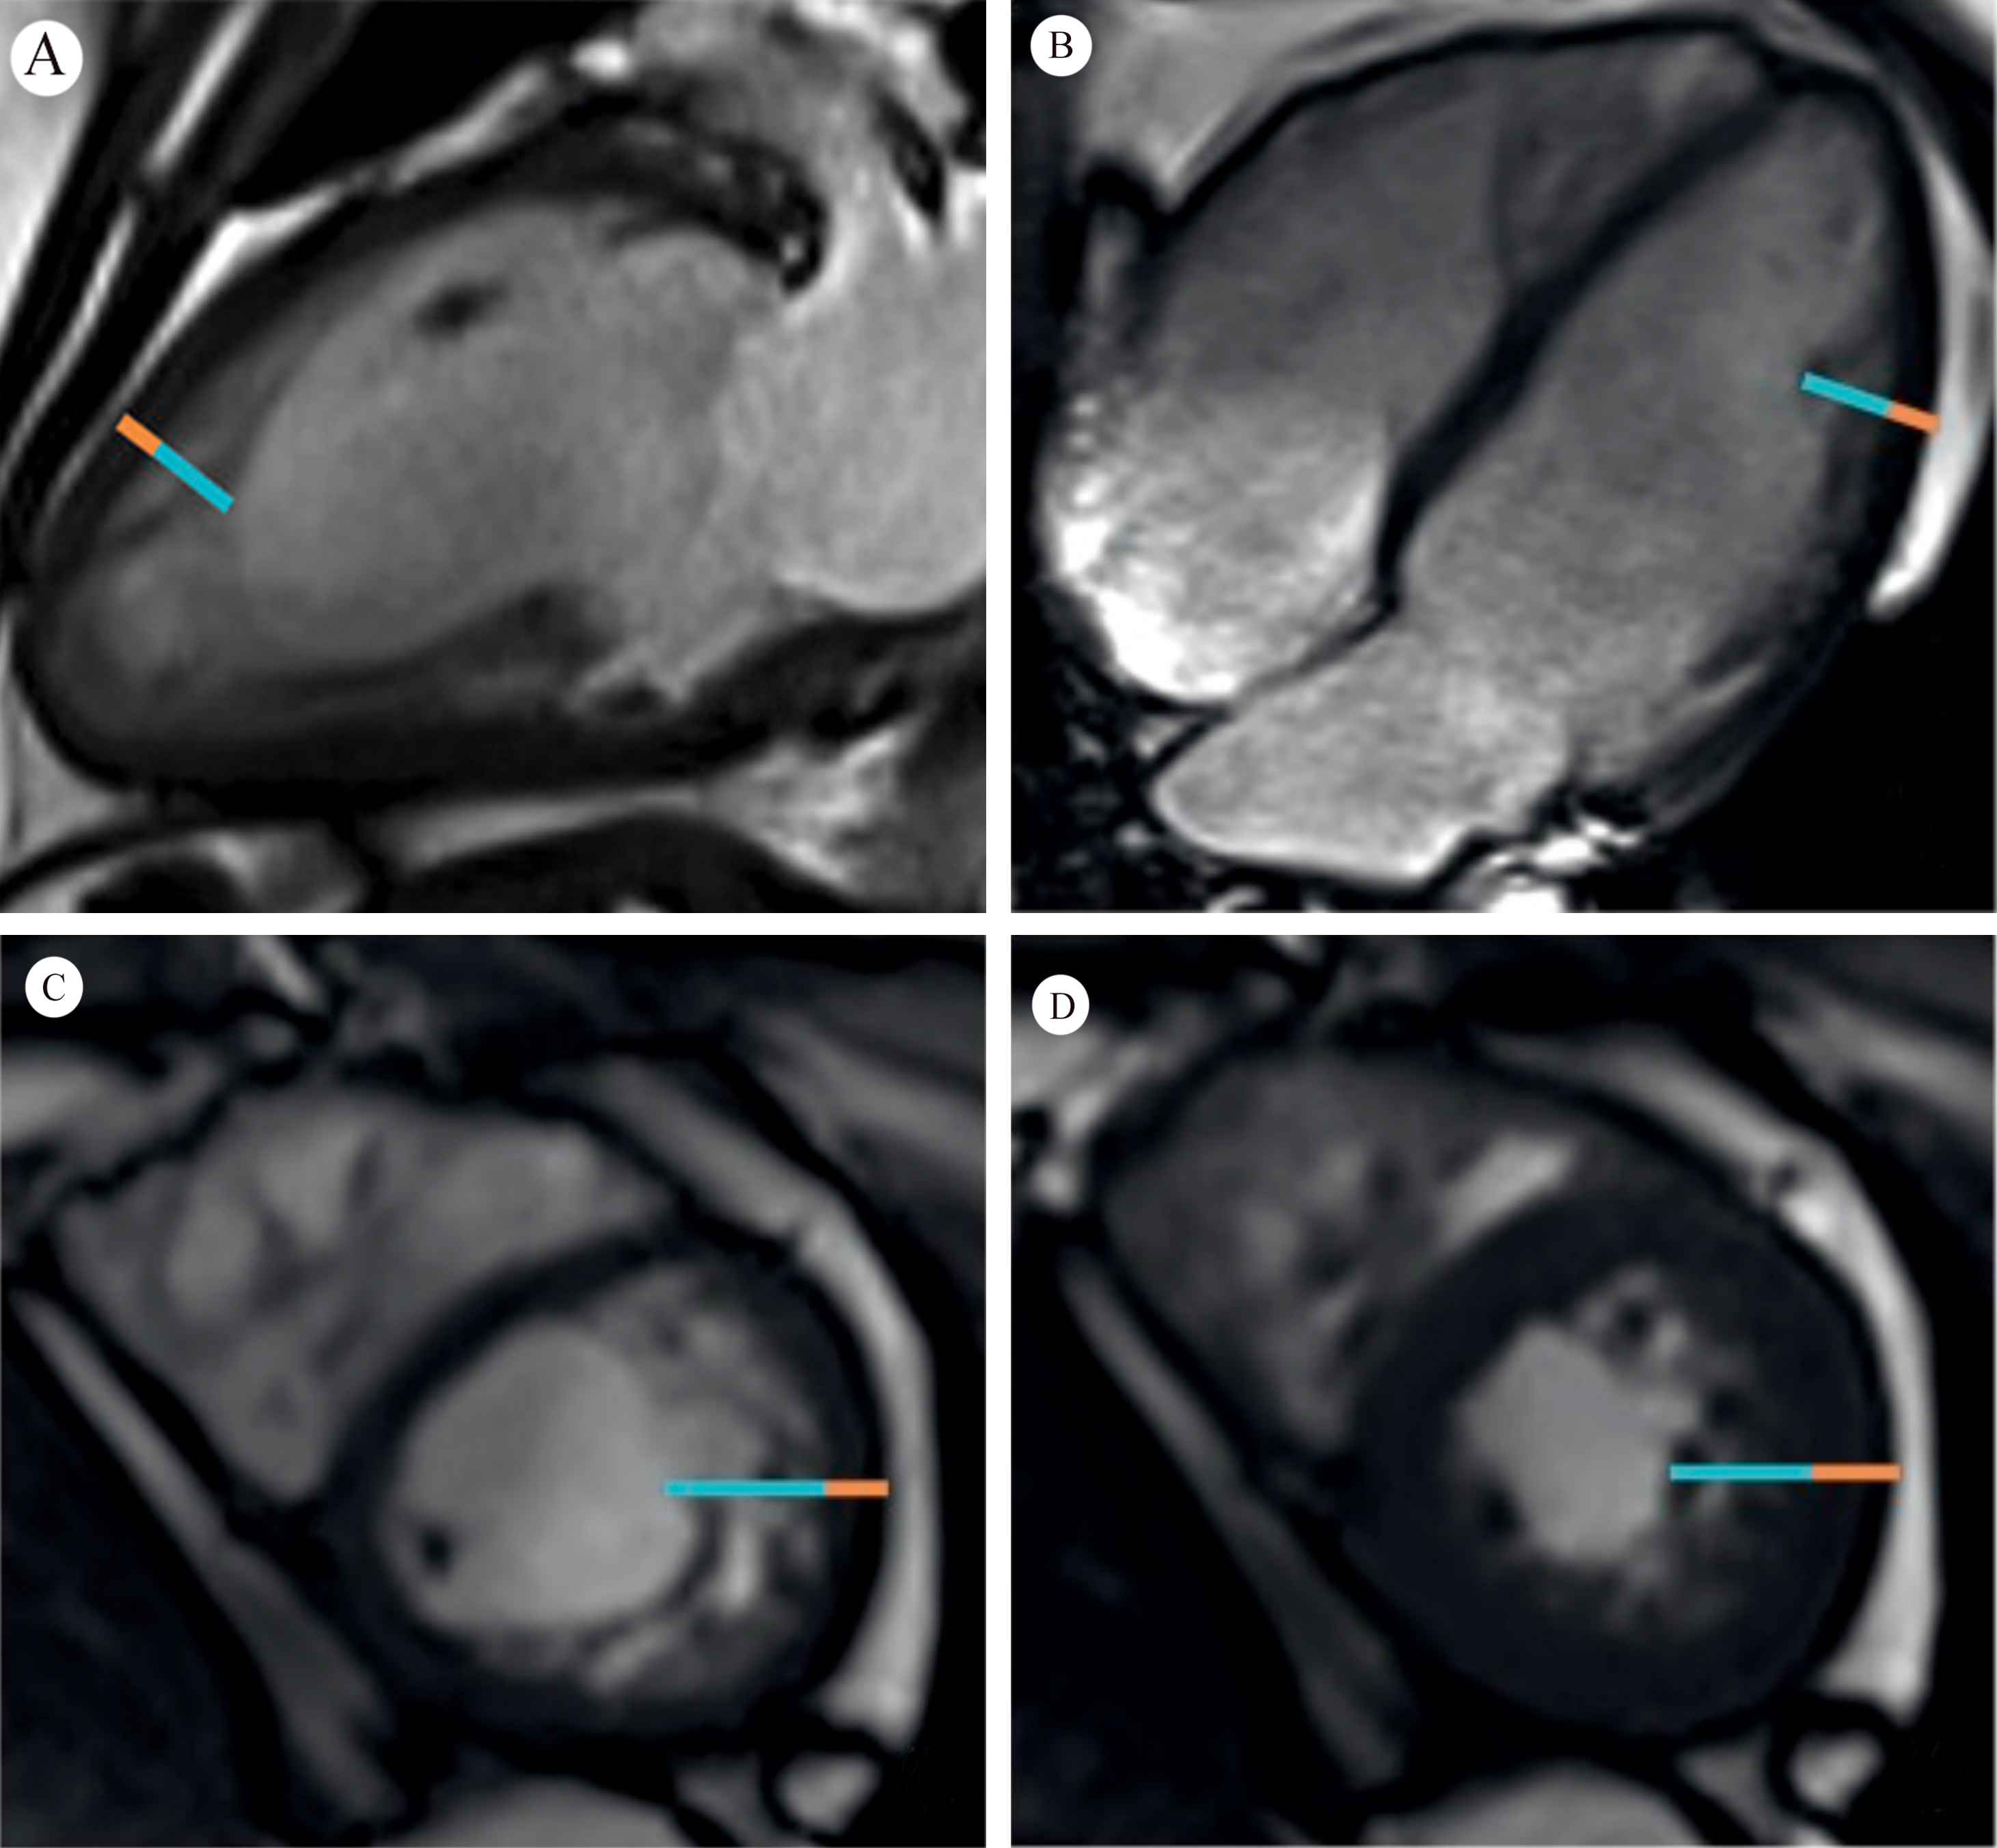

Saw-tooth cardiomyopathy (STC), first discovered in 2009 [1, 2], is a rare form of left ventricular cardiomyopathy, mainly affecting the apex and middle segment of the left ventricular wall and inferior wall. It may be evident in transthoracic echocardiography on admission. In most reported cases cardiac magnetic resonance (CMR) can provide a clearer view of the internal structure of the heart, with multiple dense myocardial protrusions similar to saw-tooth like crypts. These differ from left ventricular noncompaction (LVNC), which is characterized by noncompact myocardium in the layer of finely trabeculated myocardium adjacent to a layer of compacted myocardium [3]. The clinical course of STC ranges from asymptomatic to acute heart failure, and it can also be associated with a variety of cardiac complications. Typical images for STC are shown in Fig. 1 (Ref. [2]), and for LVNC in Fig. 2 (Ref. [3]) for comparison.

Fig. 2.Orange line = compacted myocardium; Blue line = noncompacted myocardium. Fig. 2A,B demonstrate long axis noncompaction ratio measurement, with a maximum ratio of 3.4. Fig. 2C,D demonstrate a short axis noncompaction ratio at diastole of 3.6, and a systole of 2.2, respectively (Fig. 2 is cited from Weir-McCall JR, et al. [3]).